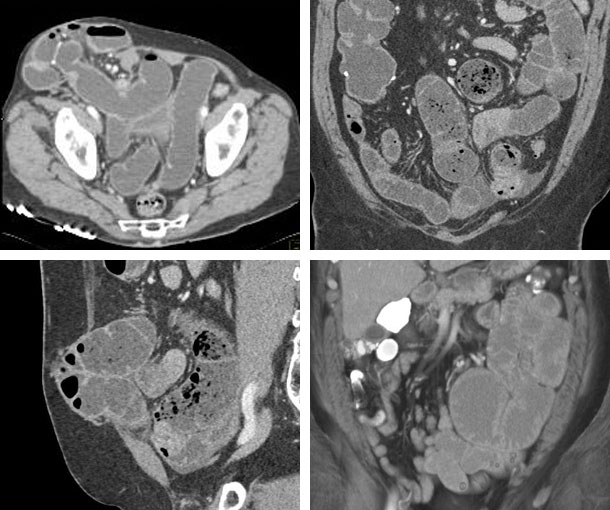

Incisional Hernia CT Findings

- Protrusion of abdominal viscera through a defect in the myofascial tissues of the abdominal wall

- Results from surgery or trauma

- Can be at site of trocar placement from laparoscopic surgery